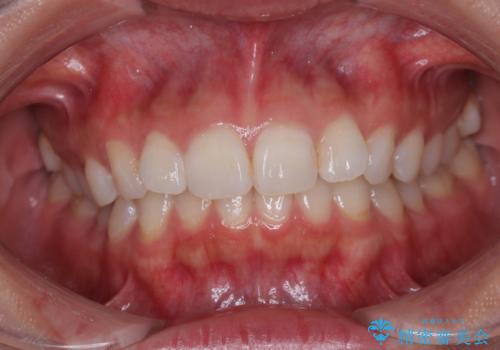

- 前歯のデコボコと突出感を気にして来院された患者様です。

極力目立たない装置を希望とのことで、インビザラインを用いて非抜歯で矯正治療を行うこととしました。

事前に親知らず2本を抜歯し、多少歯列を後方に移動できるように準備をした上で、なるべく歯と歯の間を削ることなくデコボコを解消できるように計画しました。

前歯の捻れを改善するとともに、口元が少しでも引っ込むように治療計画を立て、仕上げることができました。